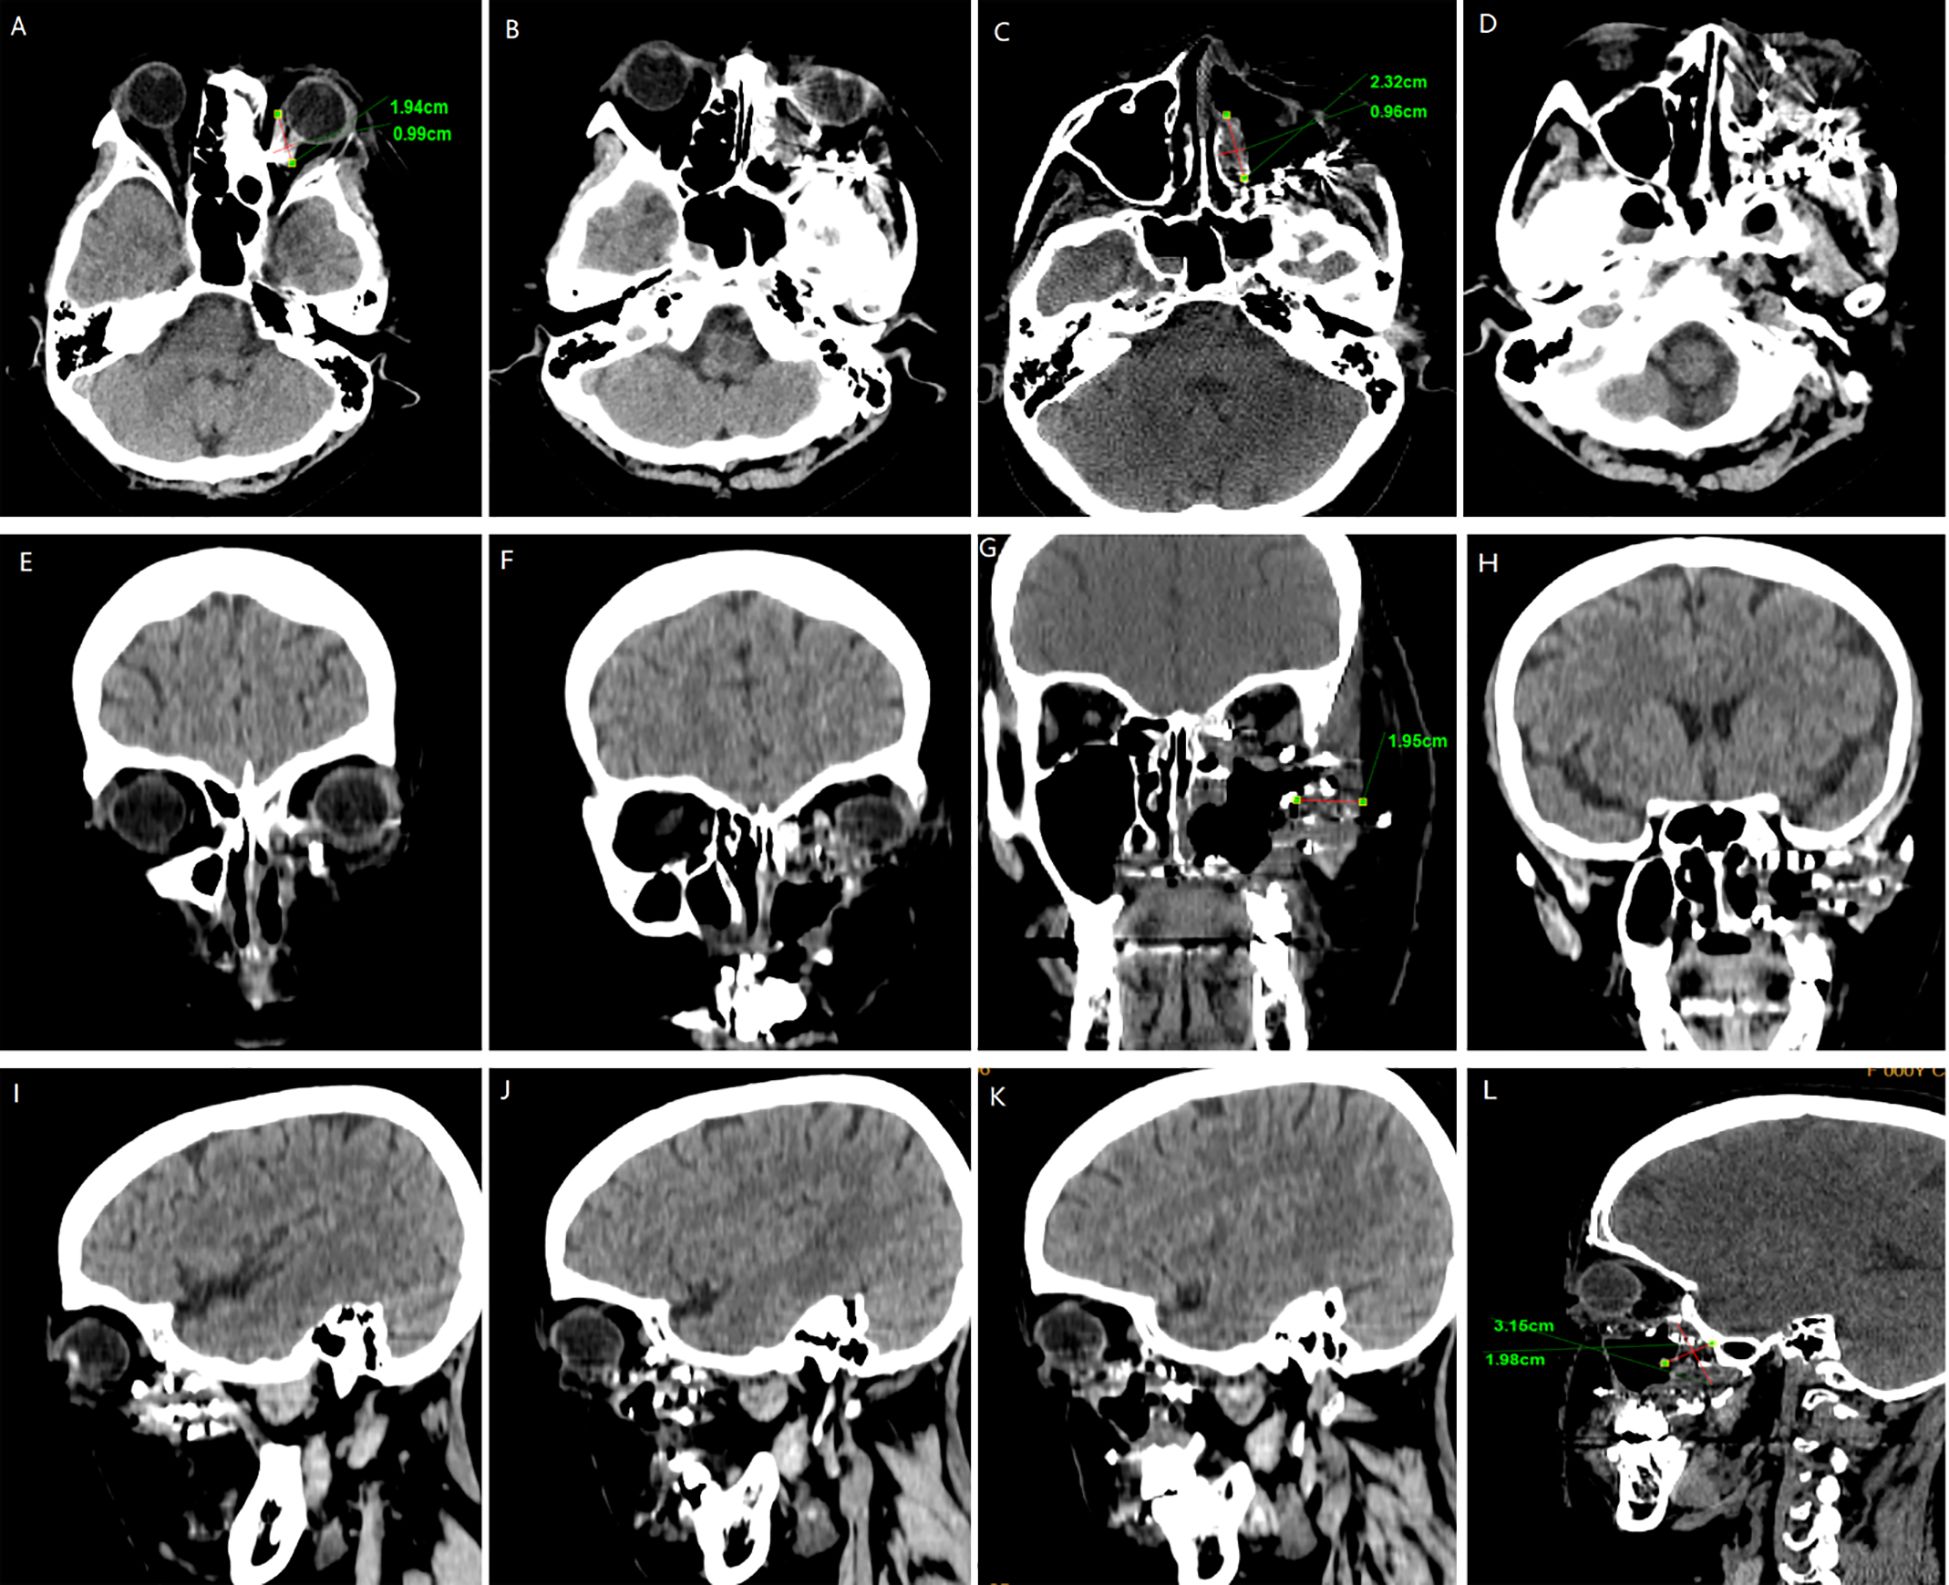

We followed up with the patient at 1 month, 3 months, 6 months, and 1 year postoperatively. After one year of follow-up, the volume of the primary tumor significantly decreased (the tumor size was approximately 5.57×4.04×6.35 cm before treatment, and 2.32×0.96×3.15 cm after treatment) (Figure 5). The intraorbital tumor decreased in size from 2.87×2.12×3.52 cm to 1.94×0.99×2.78 cm.The compression of the optic nerve by the tumor was alleviated, and both visual field and vision showed signs of recovery. The proptosis of the eyeball was significantly improved. The swelling and deformity of the eye were markedly improved, resulting in a more natural facial appearance (Figure 6). The patient’s visual acuity improved significantly from 20/200 (LogMAR 1.0) preoperatively to 20/30 (LogMAR 0.2) at 1 year postoperatively. The patient’s quality of life was significantly enhanced. No complications such as radiation-induced cataracts, optic neuropathy, or cerebral edema were observed during the last follow-up in March 2025.

Figure 5. CT surveillance findings: (A–D) Axial CT image. (E–H) Coronal CT image. (I–L) Sagittal CT image (12-month follow-up).